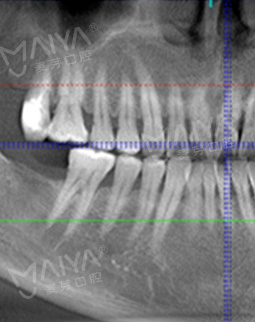

今天很早来到了院内,恰逢这里启动疑难缺牙修复工程,全城征集疑难缺牙案例,我果断报了名。由于缺牙时间长,牙槽骨吸收严重,骨量不足,给种牙带来了一定的难度,符合征集条件,于是很荣幸成为了"疑难种牙直播间"的案例主角。

拍了片子,医生指出牙周膜增宽,左上根尖部阴影大,面部有稍微萎缩,为我制定了数字化精确种牙技术,其实也很好奇,现在种牙到底有多精确多快速,和医生约定好了时间,下次直接种牙。